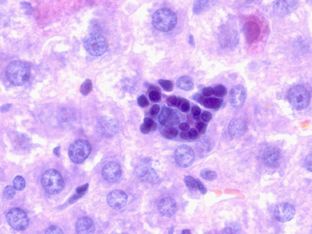

Помимо особенностей окраски, в гистологических препаратах форменные элементы крови имеют иную форму, поскольку они не распластаны на стекле, а находятся свободно либо бывают сдавлены окружающими структурами. На рис. 1-3 представлены ситуации, когда от выявления лейкоцитов определённого вида в исследуемых тканях зависит постановка диагноза.

Рисунок 3 – Лимфатический узел собаки при гнойном лимфадените

Рисунок 3 – Лимфатический узел собаки при гнойном лимфадените. Препарат содержит множество сегментоядерных нейтрофильных гранулоцитов